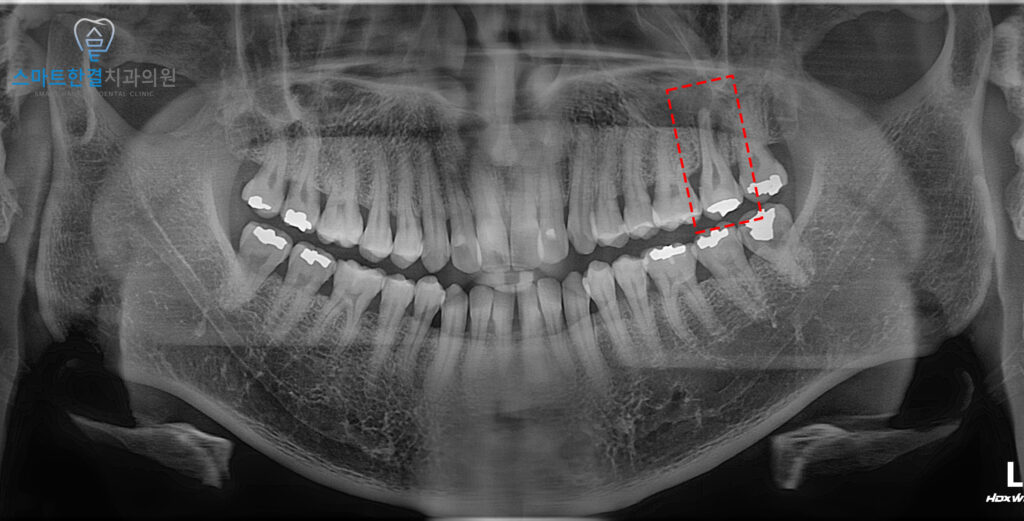

25.01

파노라마 상에서

치아 뿌리 끝으로 염증이 잡혀있는 모습을

확인할 수 있었어요.

이는 치아 내부 감염이

치근단까지 진행된 상태로,

주변 골 조직의 손상까지

동반된 것으로 판단할 수 있었는데요.